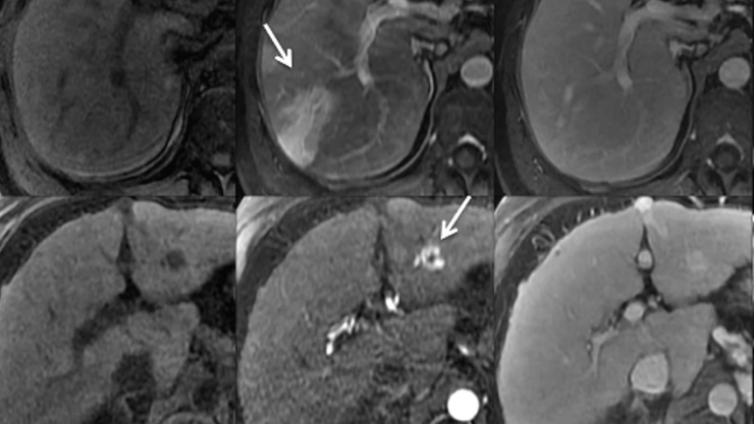

12 07月 放射科 骨巨细胞瘤(Giant cell tumour of bone,GCTB) 骨巨细胞瘤(Giant cell tumour of bone,GCTB)◆ 容易局部侵袭、少见远处转移的中间型骨肿瘤◆ 占原发骨肿瘤的4~5%,占20%的良性骨肿瘤,伴ABC样10-14%◆ 发病高峰在(20-30)20-45岁之间,约10%的病例发生10-20岁◆ 亚型> 骨巨细胞瘤(GC...

11 07月 放射科 动脉瘤样骨囊肿、及其常见肿瘤 动脉瘤样骨囊肿(Aneurysmal bone cyst; ABC)◆ 富含破骨性巨细胞的良性肿瘤,相关基因USP6◆ 罕见,原发骨肿瘤的2.5%/1-6%◆ 年龄:任何年龄,10-30岁多见,约80%<20岁◆ 性别:女性稍多/F=M◆ 部位:任何骨骼常见:长管状骨干骺端(70%):股骨、胫...